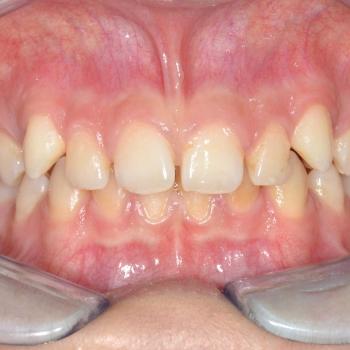

Nándi és édesanyja esztétikai okokból, a kiálló szemfogak és a réses felső metszőfogak miatt kerestek fel. Az első konzultáció alkalmával ezen túlmenően komoly helytöbbletet fedeztünk fel az alsó fogívben, illetve mélyharapást és a szemfogak területén Class II-es harapási eltérést tapasztaltunk.